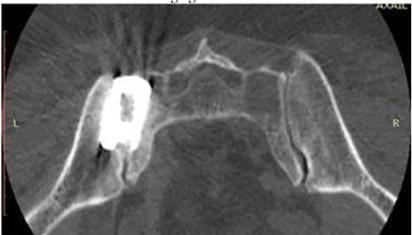

| ● | Radiographic Confirmation of Bridging Bone Fusion of the SI-Joint |

The Catamaran System is a singular implant designed with several proprietary components which allow for it to be explicitly formatted to address the SI-Joint with a single approach and implant. This contrasts with several competitive implant systems that require multiple approach pathways and implants to achieve fixation. In addition, the inferior-posterior approach is designed to be direct to the joint and through limited anatomical structures which may minimize the morbidity of the approach. The implant features a patented dual pontoon open cell design which enables the clinician to pack the pontoons with the patient’s own autologous bone designed to promote bone fusion across the joint. The Catamaran System is designed specially to resist vertical shear and rotation of the joint in which it was implanted, helping stabilize the joint in preparation for eventual fusion.

Tenon also has developed a proprietary 2D placement protocol as well as a protocol for 3D navigation utilizing the latest techniques in spine surgery. These Tenon advancements are intended to further enhance the safety of the procedure and encourage more physicians to adopt the procedure.